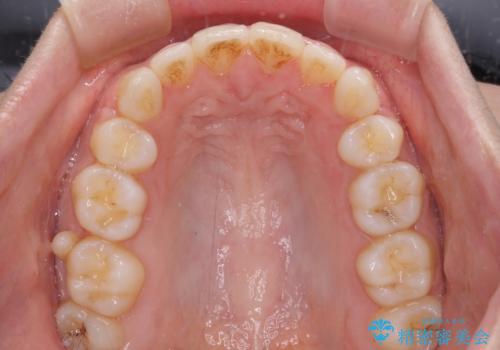

- 前歯のデコボコと口元の突出感を気にして来院された患者様です。

上下左右第一小臼歯4本を抜歯し、ワイヤー装置にて口元を引っ込めるよう矯正治療を行うこととしました。

叢生が強かったため、口元の突出感の改善には限界がありましたが、横側からも口元が引っ込んだ感じが分かるほど改善されました。